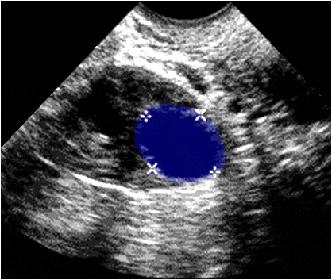

Ecografía ginecológica que muestra el contorno del ovario y en su interior un folículo en desarrollo (azul).